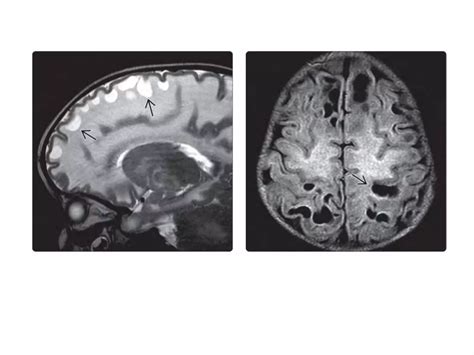

Diagnosing White Matter Disease typically relies on advanced imaging techniques rather than just clinical observation. Physicians look for specific patterns of damage that distinguish this condition from others like Alzheimer’s or stroke.

MRI (Magnetic Resonance Imaging) The gold standard for identifying white matter hyperintensities (bright spots on the scan indicating damage).